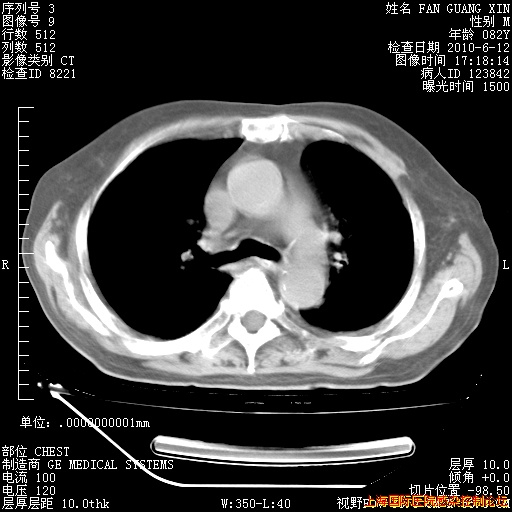

今天复查CT

今天CT

整整相隔30天的肺部CT好像有所好转啊。甲强龙减量第3天,需要观察体温。

海管,自昨日你和我通完话后,不知您岳父消化道症状有无缓解?体温怎样?阅读7.12日胸部ct,个人认为目前激素治疗是有效的,甲强龙减量是适宜的。因在抗痨治疗,需密切观察肝功、肾功能和血常规。不过,老年、长期住院和大量使用激素,很担心菌群失调发生